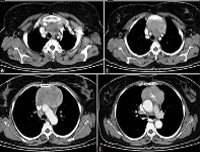

МРТ молочной железы. Послойное сканирование органов грудной клетки с помощью радиочастотной энергии в сильном магнитном поле. Это позволяет проводить неинвазивное исследование легких, плевры, органов средостения, тканей молочной железы и очищать данные от других инструментальных методов визуализации (рентген, КТ молочной железы). МРТ молочных желез наиболее полезна для диагностики поражений легких и средостения и оценки их проникновения в окружающие структуры. МРТ может обнаружить поражения лимфатических узлов (с лимфогранулематозом, туберкулезом, метастазированием ), Патологическое развитие органов, патологию брюшной аорты (аневризма, диссекция), экссудативный плеврит и перикардит При наличии показаний МРТ органов грудной клетки выполняется с контрастным усилением.

Магнитно-резонансная томография грудной клетки использовалась в клинической практике в течение относительно короткого времени с конца 1970-х годов. В России исследование было доступно примерно на 10-15 лет позже, чем в европейских странах. В последние годы магнитно-резонансная томография грудной клетки была продемонстрирована при исследовании органов средостения и других структур этой анатомической зоны. Возможность получения нескольких изображений в слоях с последующим формированием трехмерной модели позволяет идентифицировать патологические очаги на доклинической стадии, безопасно определять их местоположение, точно дифференцировать различные заболевания в тех случаях, когда другие методы недостаточно информативны. Магнитно-резонансная томография грудной клетки превосходит компьютерную томографию, УЗИ и рентгенографию с точным определением границ патологических очагов. Еще одним значительным преимуществом магнитно-резонансной томографии является отсутствие радиационного воздействия.

МРТ грудной клетки используется для оценки состояния легких, плевры, органов и тканей средостения (трахеи, пищевода, кровеносных сосудов, лимфатических узлов, тимуса, жировой ткани), а также мышц и тканей. подкожная жировая клетчатка Диагностическая ценность МРТ при исследовании легочной ткани зависит от типа патологии, многие заболевания лучше или с той же точностью, что и при сканировании. МРТ грудной клетки менее информативна при исследовании ребер и грудины, но иногда успешно используется для выявления новообразований костной и хрящевой структур, для диагностики травматических повреждений и аномалий развития.